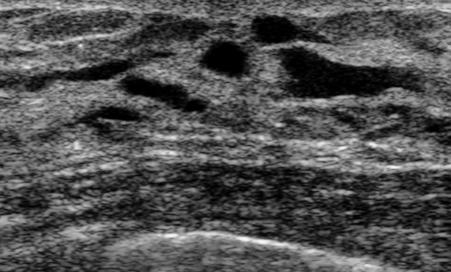

The target dataset was developed from 35 breast ultrasound scans that were segmented by an image-processing expert with extensive experience in breast lesion segmentation (the second author). The images, collected from the Web, are of different dimensions, ranging from to pixels (Figure 3, images resized for sake of illustration). These are the same images used to introduce EFIS originally [1].

Ultrasound images are generally difficult to segment, primarily due to the presence of speckle noise and low level of local contrast. It should be noted that the segmentation of ultrasound actually does require a complete processing chain, (including proper preprocessing and post-processing steps). However, the purpose of using these images was solely to demonstrate that the accuracy of the segmentation can be increased with the application of SC-EFIS.